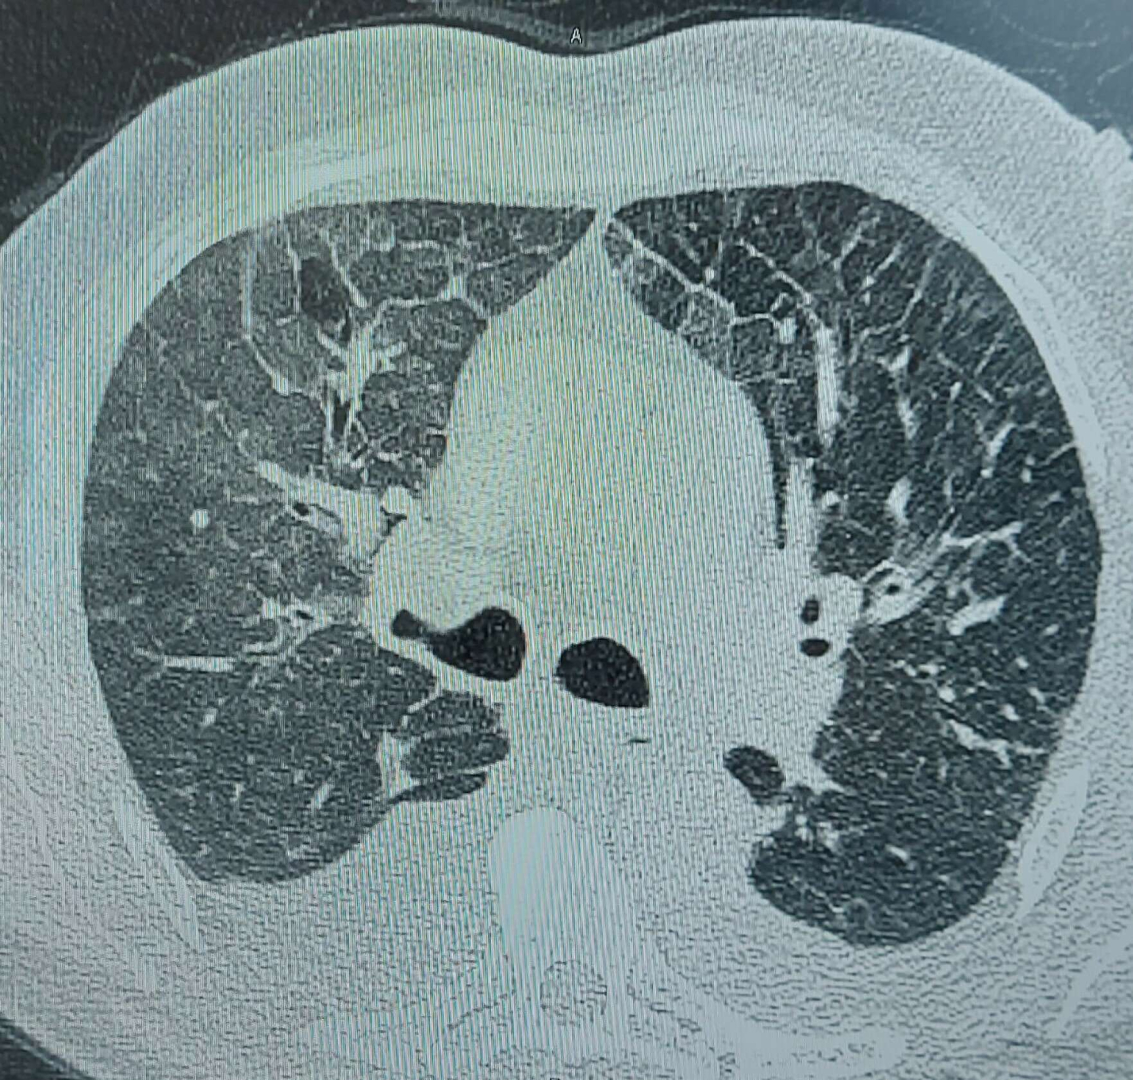

Yapılan incelemelerin ardından tedaviye başlanan hasta, hayati tehlikeyi atlattı. Hastaya müdahaleyi yapan VM Medical Park Bursa Hastanesi Göğüs Hastalıkları Uzmanı Dr. İbrahim Ocak, “Son bir hafta içinde iki hastam acil bölümünden geldi. Biri yaygın kemik ve eklem ağrıları, halsizlik, yoğun kırgınlık, kandaki oksijen yüzdesi yüzde 74’lere kadar inmiş bir haldeydi. Acilde hastayı değerlendirdikten sonra tomografi ve kan tahlili yaptık. Kan tahlillerinde ürekratin elektrolit dengesinin çok değişmiş olduğunu gördük. Neredeyse tüm vücudunun elektrolitleri değişmiş ve zararlı düzeye gelmişti. Çektiğimiz tomografide de akciğerde ploraze dediğimiz sıvı birikmesi olmuş, kalp enzim değerleri artmış ve enfeksiyon değerleri yükselmişti. Niçin böyle olduğunu öğrenmeye çalışırken, hasta yaklaşık 2 aydır su diyeti yaptığını söyledi. Nasıl uyguladığını sorduğumda ise, ‘Su içiyorduk. Günde 3 öğün, maydanoz, dereotu, roka gibi sadece sebze ağırlıklı beslendik’ dedi. Hastamızı yatırdık, tedavisine başladık. Diyetini kestik ve normal beslenmeye geçtik. 3-4 gün içerisinde toparladı. Durumu şimdi daha iyi. Bende su diyetinin sosyal medyada reklamını görmüştüm. Hatta kendi hesabımda 'bu şarlatanlıktır, bu doğru değildir' yazdım. Orada eleştirilere de uğradım. Ama hala aynı şeyi söylüyorum” dedi. “HER HASTAMA DİYETİ BENDE TAVSİYE EDİYORUM”

Yapılan incelemelerin ardından tedaviye başlanan hasta, hayati tehlikeyi atlattı. Hastaya müdahaleyi yapan VM Medical Park Bursa Hastanesi Göğüs Hastalıkları Uzmanı Dr. İbrahim Ocak, “Son bir hafta içinde iki hastam acil bölümünden geldi. Biri yaygın kemik ve eklem ağrıları, halsizlik, yoğun kırgınlık, kandaki oksijen yüzdesi yüzde 74’lere kadar inmiş bir haldeydi. Acilde hastayı değerlendirdikten sonra tomografi ve kan tahlili yaptık. Kan tahlillerinde ürekratin elektrolit dengesinin çok değişmiş olduğunu gördük. Neredeyse tüm vücudunun elektrolitleri değişmiş ve zararlı düzeye gelmişti. Çektiğimiz tomografide de akciğerde ploraze dediğimiz sıvı birikmesi olmuş, kalp enzim değerleri artmış ve enfeksiyon değerleri yükselmişti. Niçin böyle olduğunu öğrenmeye çalışırken, hasta yaklaşık 2 aydır su diyeti yaptığını söyledi. Nasıl uyguladığını sorduğumda ise, ‘Su içiyorduk. Günde 3 öğün, maydanoz, dereotu, roka gibi sadece sebze ağırlıklı beslendik’ dedi. Hastamızı yatırdık, tedavisine başladık. Diyetini kestik ve normal beslenmeye geçtik. 3-4 gün içerisinde toparladı. Durumu şimdi daha iyi. Bende su diyetinin sosyal medyada reklamını görmüştüm. Hatta kendi hesabımda 'bu şarlatanlıktır, bu doğru değildir' yazdım. Orada eleştirilere de uğradım. Ama hala aynı şeyi söylüyorum” dedi.